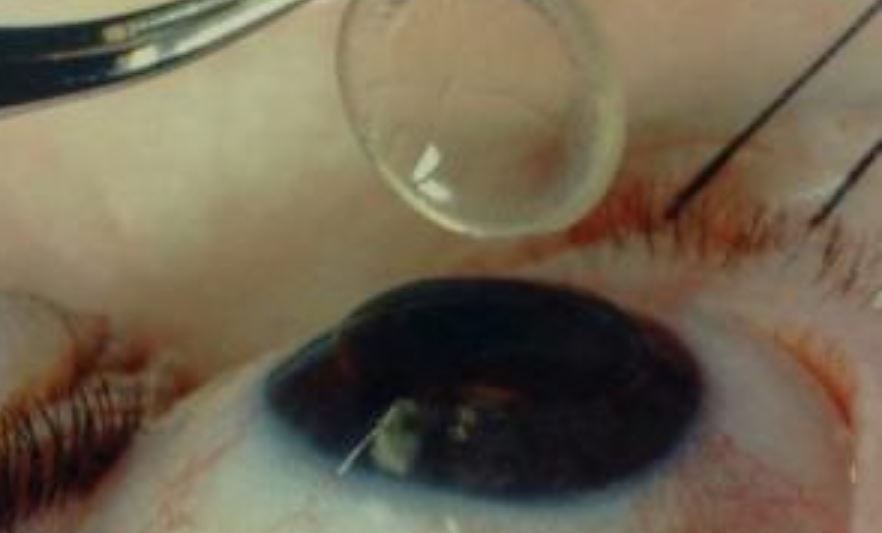

Sul posto è giunta un’équipe del Coordinamento trapianti dell’ospedale “Renzetti”, guidata da Fabrizio Fumarola, anestesista, e composta da Tiziana Marsilio, oculista, e Marco Di Nella, strumentista, che ha provveduto al prelievo delle cornee. Non è stato possibile fare lo stesso con altri organi, resi inutilizzabili dalla malattia.